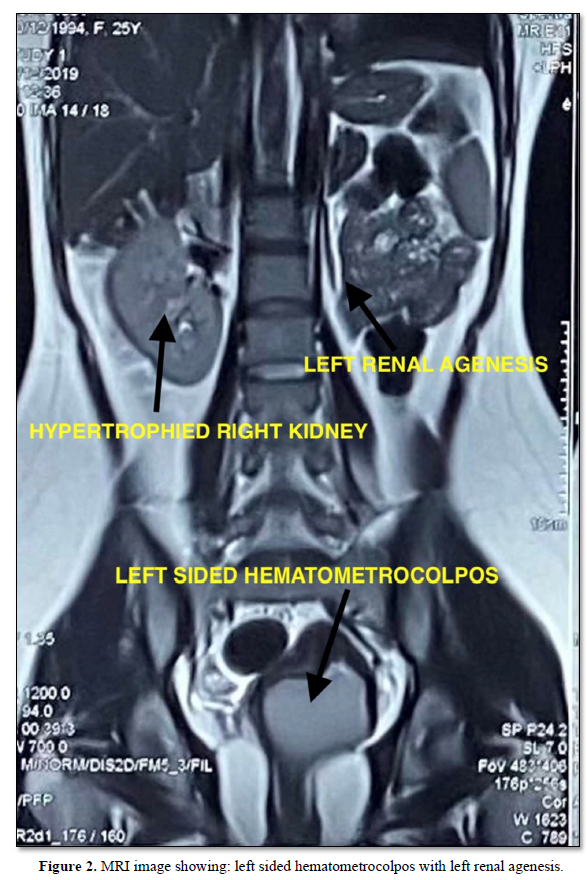

This case is a 25-year-old nulligravida presented with complaints of dull aching pain in the abdomen with worsening dysmenorrhea for the past 10 months. She was married for 3 years. The patient attained menarche at the age of 17 years and had regular menstrual cycles, once every 28 days with 7- to 8- day duration. General physical examination and abdominal examination was within normal limits. Vaginal examination revealed normal right sided cervix which was felt high up and left vaginal wall bulge which was non-tender and cystic inconsistency. Same findings were confirmed by per rectal examination. Ultrasound revealed a bicornuate uterus, left sided endometrioma with hematocolpos. The left kidney was not visualized. Magnetic resonance imaging confirmed the same findings (Figure 2).

Laboratory tests were within normal limits and CA-125 was 14.71. Thus, the patient was diagnosed with OHVIRA Syndrome. Under general anesthesia vaginoscopy was performed and vaginal septum resection was done. During vaginoscopy a bulge was seen on the left lateral wall which was extending up to introitus. A normal right sided cervix was seen. Incision was given over the bulge using a resectoscope on the upper end of the bulge. After the drainage of hematocolpos, the left sided pinpoint hole cervix was identified. Vaginal septum was excised and reefed. On follow up patient had dysmenorrhea only. She conceived twice after ovulation induction therapy. First one was a missed abortion in first trimester. In her second conception, currently her period of gestation is around 20 weeks and uncomplicated till date. Her antenatal ultrasounds showed left sided 3X3 cm endometrioma and live intrauterine pregnancy in the right horn. Her aneuploidy screening is within normal limits. Anomaly scan was normal with cervical length of 3.2 cm.